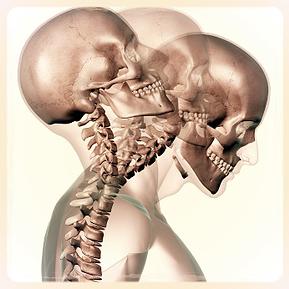

Tenha uma boa noite de sono conhecendo a postura correta para dormir

Ter uma boa noite de sono não é apenas uma necessidade de descanso mental e físico: durante o sono ocorrem vários processos metabólicos que, se alterados, podem afetar o equilíbrio de todo o organismo a curto, médio e, mesmo, a longo prazo.A pessoa que tem noites mal dormidas apresenta menor vigor físico, envelhece mais precocemente, […]